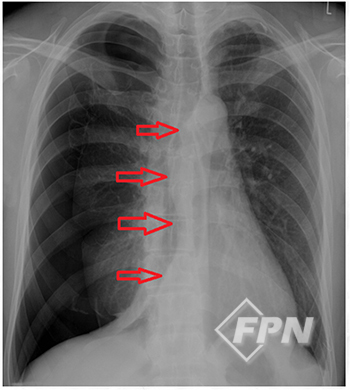

▲ 긴장성 기흉 환자의 X-ray

긴장성 기흉은 자연 기흉과 외상성 기흉 어느 경우에나 발생할 수 있습니다.

긴장성 기흉은 한쪽 폐의 기흉으로 인해 심장이 반대편으로 밀리면서 대정맥이 꺾이는 응급상황입니다. 어떤 원인에 의해 환자가 숨을 들이 쉴 땐 공기가 흉강 속으로 유입되지만 숨을 내쉴 땐 흉강속의 공기가 배출되지 못해 흉강 속의 압력이 점점 높아지는 상태를 말합니다.

꺾인 대정맥 때문에 정맥의 혈액이 심장으로 돌아오지 못해 쇼크 상태가 되고 한쪽 폐가 갑자기 기능부전에 빠지게 됩니다. 심한 호흡곤란과 청색증, 저혈압 등이 발생해 치명적인 상태에 이를 수 있습니다. 즉각적인 응급조치가 필요합니다.